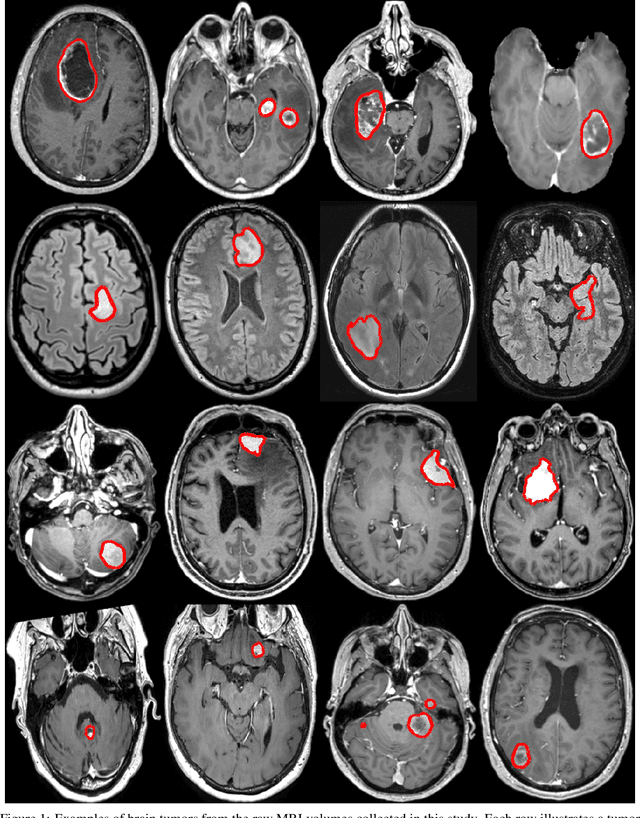

Abstract:For patients suffering from brain tumor, prognosis estimation and treatment decisions are made by a multidisciplinary team based on a set of preoperative MR scans. Currently, the lack of standardized and automatic methods for tumor detection and generation of clinical reports represents a major hurdle. In this study, we investigate glioblastomas, lower grade gliomas, meningiomas, and metastases, through four cohorts of up to 4000 patients. Tumor segmentation models were trained using the AGU-Net architecture with different preprocessing steps and protocols. Segmentation performances were assessed in-depth using a wide-range of voxel and patient-wise metrics covering volume, distance, and probabilistic aspects. Finally, two software solutions have been developed, enabling an easy use of the trained models and standardized generation of clinical reports: Raidionics and Raidionics-Slicer. Segmentation performances were quite homogeneous across the four different brain tumor types, with an average true positive Dice ranging between 80% and 90%, patient-wise recall between 88% and 98%, and patient-wise precision around 95%. With our Raidionics software, running on a desktop computer with CPU support, tumor segmentation can be performed in 16 to 54 seconds depending on the dimensions of the MRI volume. For the generation of a standardized clinical report, including the tumor segmentation and features computation, 5 to 15 minutes are necessary. All trained models have been made open-access together with the source code for both software solutions and validation metrics computation. In the future, an automatic classification of the brain tumor type would be necessary to replace manual user input. Finally, the inclusion of post-operative segmentation in both software solutions will be key for generating complete post-operative standardized clinical reports.